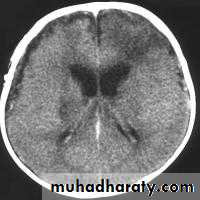

CT finding

Low attenuation of white matter ( due to the edema)

Compressing the ventricular system ( also due to edema ) specially the frontal & the body of the lateral ventricle become slit like .